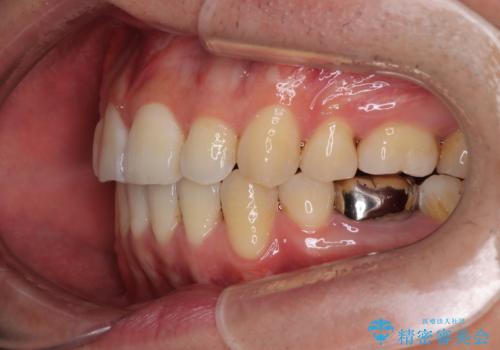

- 口元の突出感が強く、口が閉じにくいことを主訴として来院された患者さんの症例をご紹介します。

前歯部の叢生(デコボコ)も認められ、歯がきれいに並ぶためのスペースが不足している状態でした。

これらの問題を総合的に改善するため、上下左右の第一小臼歯を計4本抜歯し、スペースを確保する治療計画を立てました。

抜歯したスペースを活用して前歯を後ろへ下げることで、口元の突出感を大きく改善。

奥歯の噛み合わせがずれている「シザーズバイト」を適正に整えることで、見た目だけでなく機能性も向上し、安定した咬合が獲得できました。

口元の突出が改善され、横顔の印象が大きく変化し、口が自然に閉じやすくなりました

前歯のデコボコが整い、清掃性が向上

噛み合わせが改善し、長期的に安定する噛み合わせに